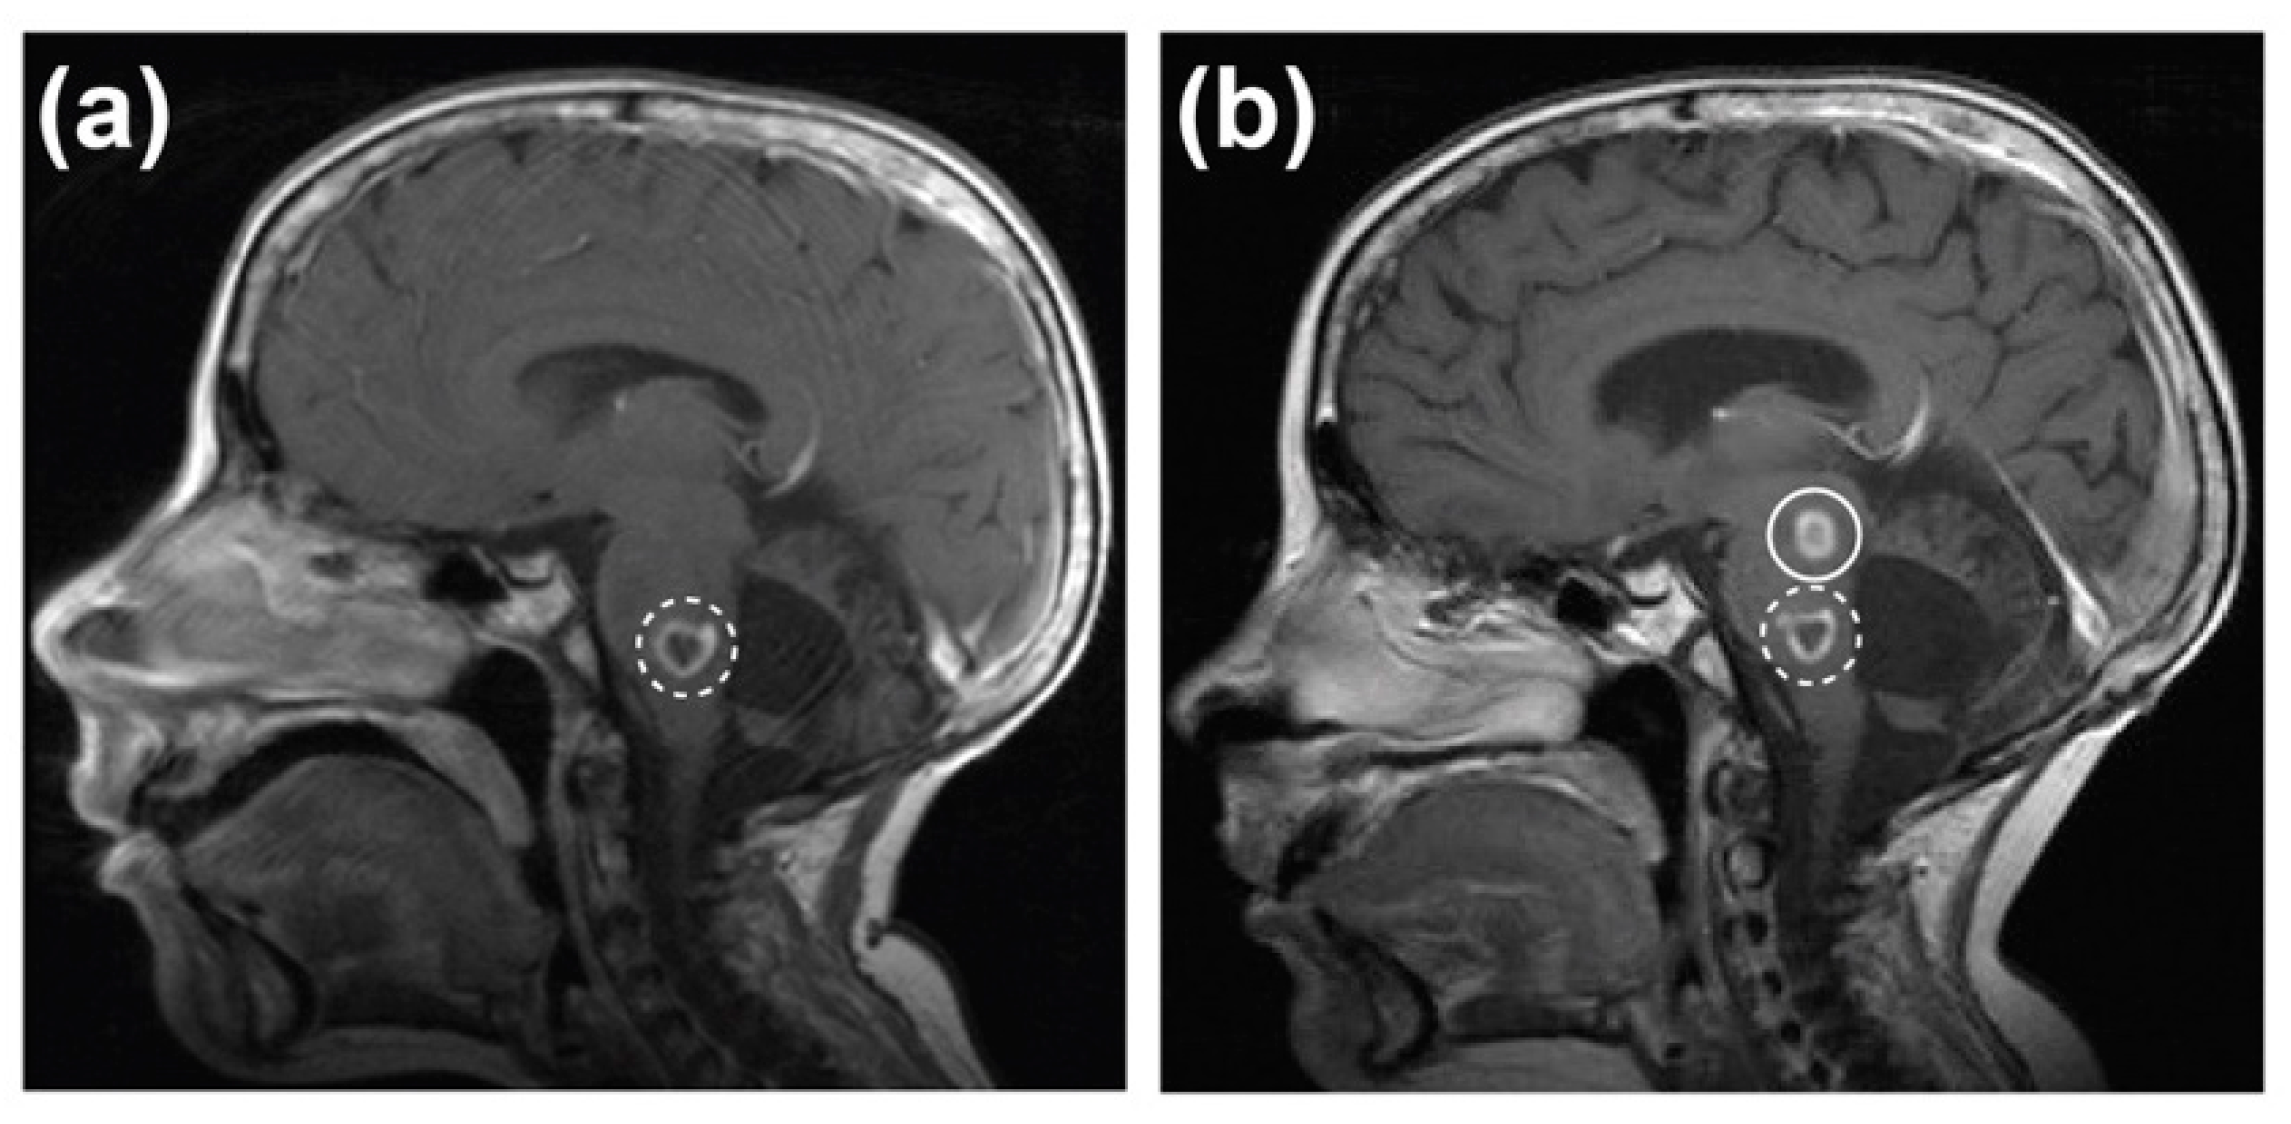

2.1. Case Report

2.2. Development of a PDX Model of RIG Following Medulloblastoma that Histologically Recapitulates the Patient Tumour